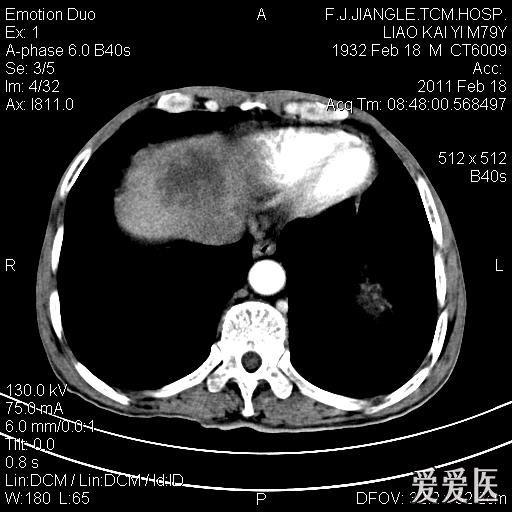

一例确诊的肝脓肿ct平扫增强

图片尺寸512x512